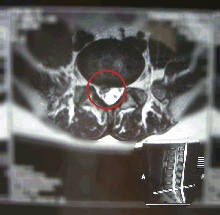

■水平断面

写真左後方(患者さん右)に飛び出しているのが、見られます。